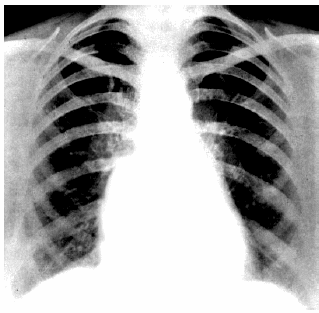

067. Какие рентгенологические признаки можно выявить у пациентки со стенозом левого атриовентрикулярного отверстия (см. рис.)?

1. Исчезновение «талии» сердца

2. Расширение аорты в восходящем отделе

3. Увеличение левого предсердия

4. Гипертрофия правого желудочка

5. Увеличение правого предсердия

067

1,3,4